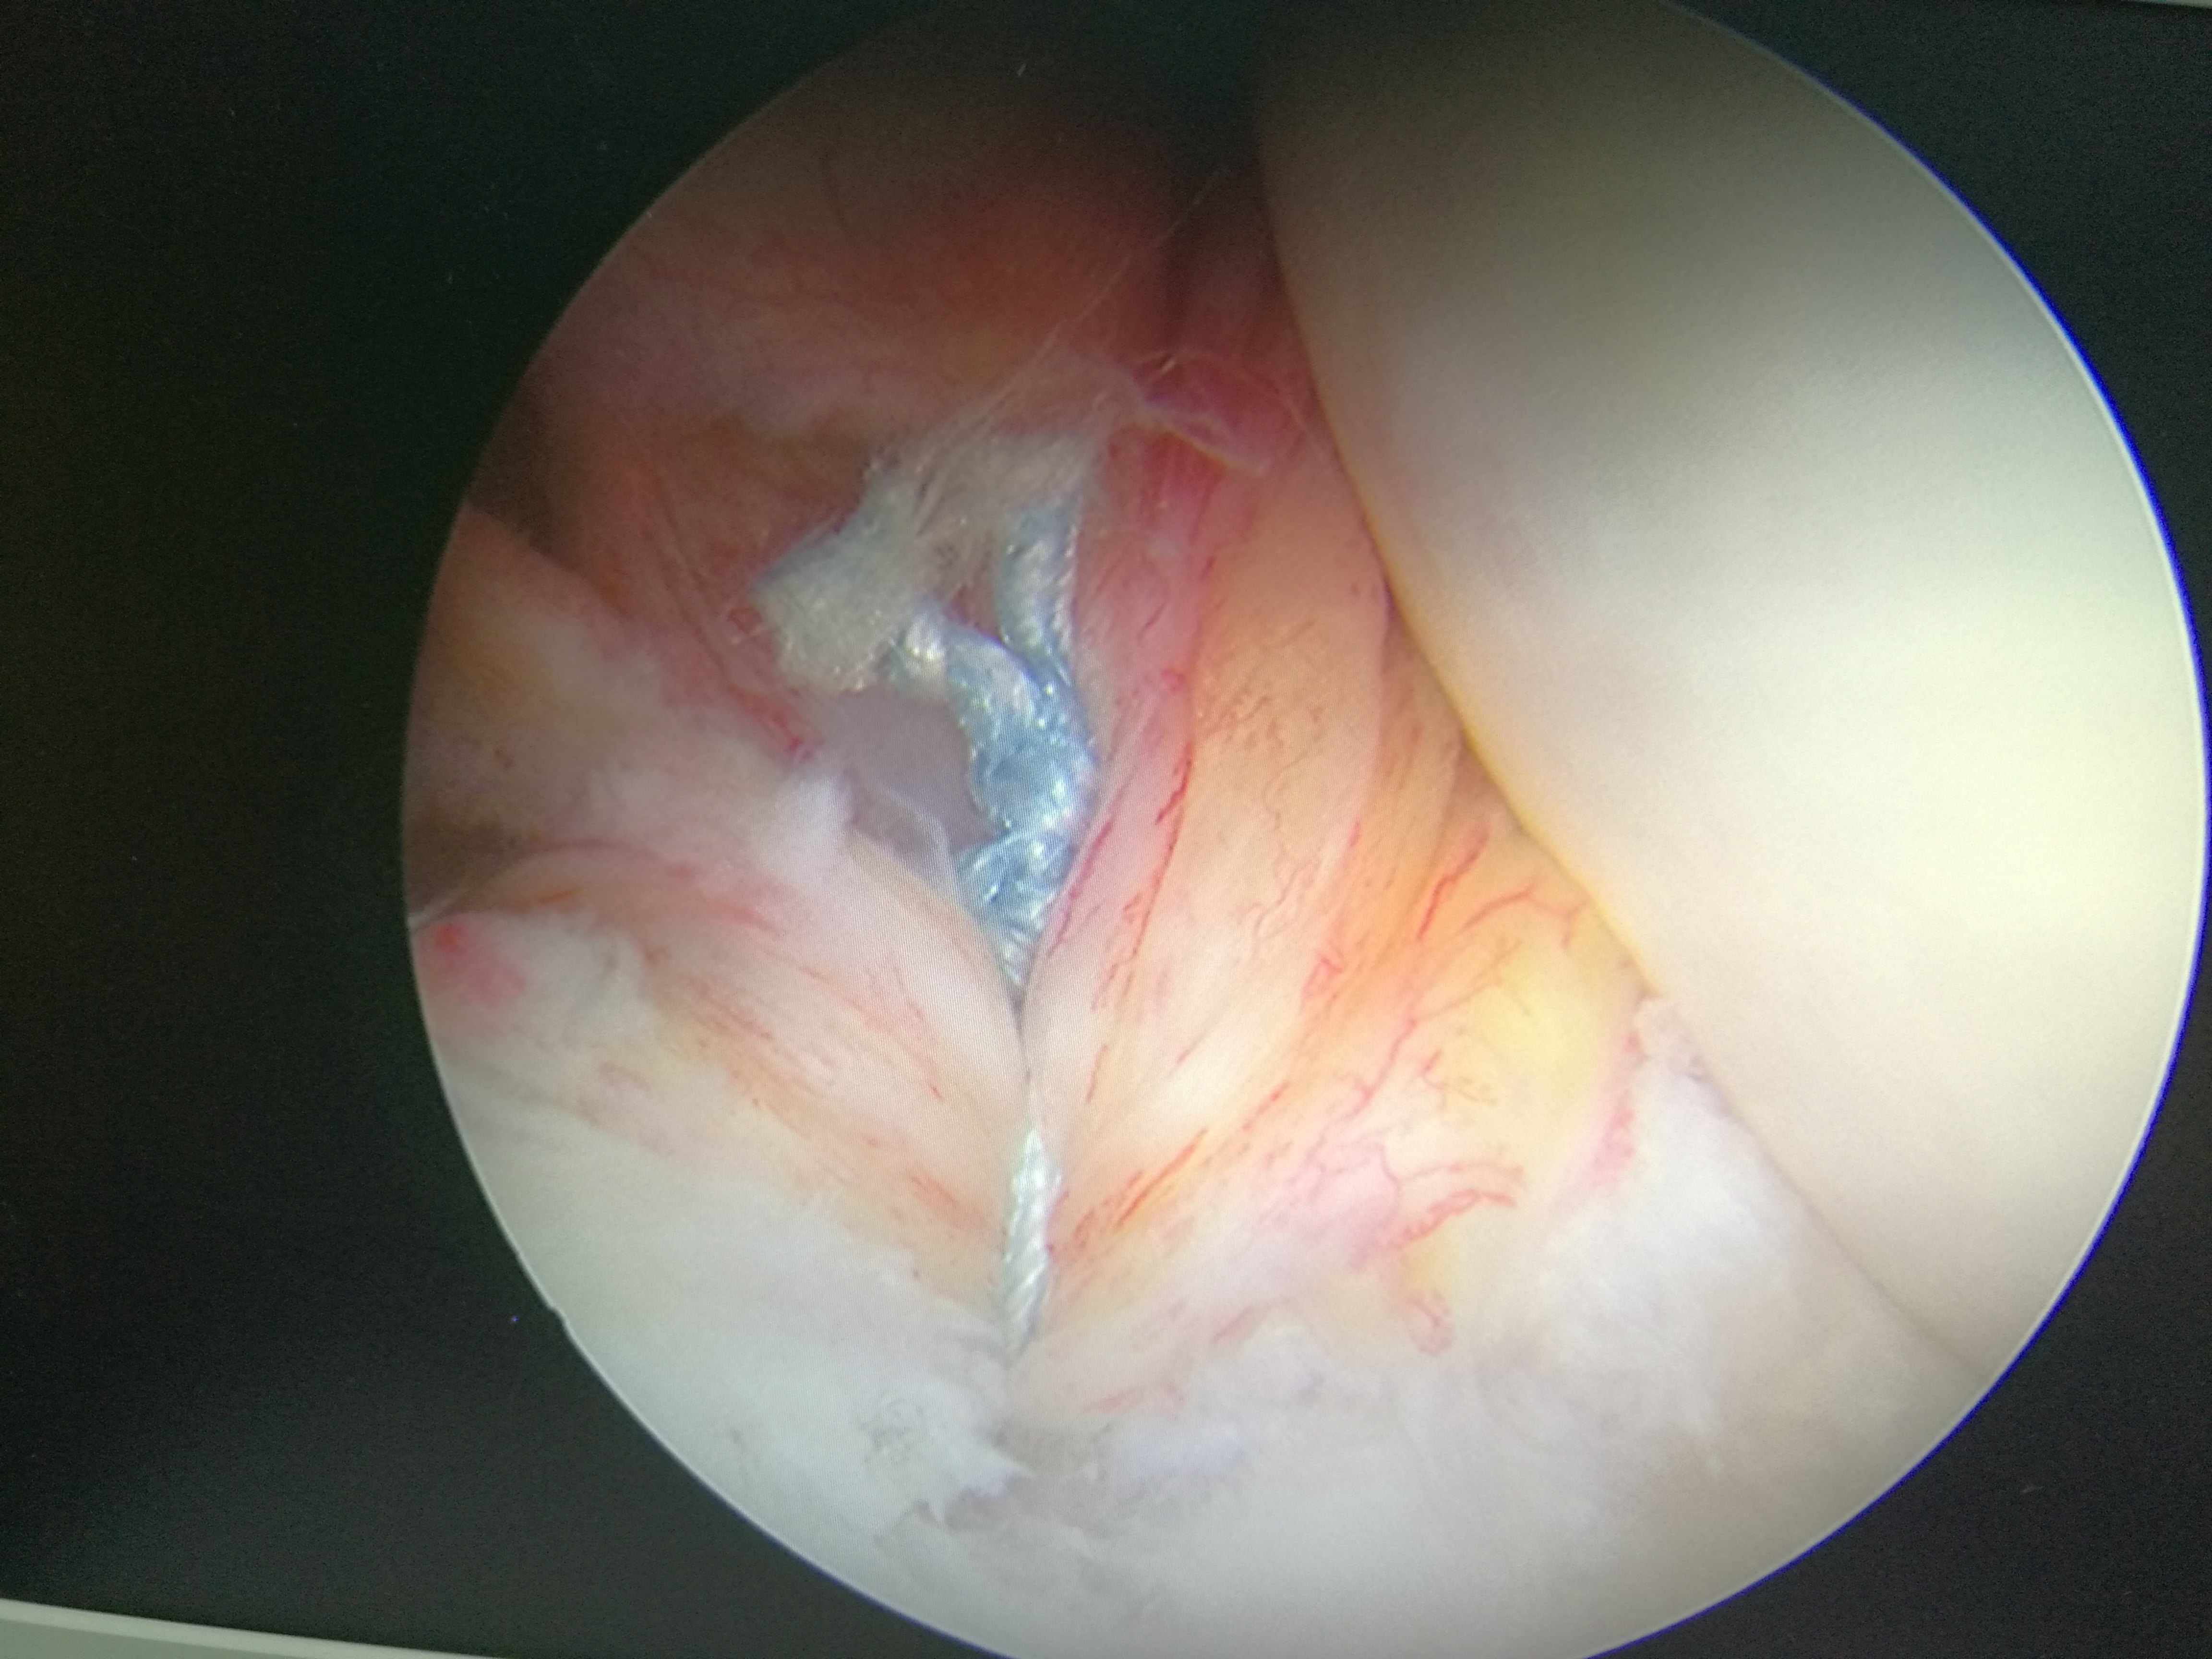

关节镜手术是一种微创手术,它以微切口,创伤小,恢复快,效果好为特点,逐渐被越来越多的人接受。在治疗关节疾病方面有着绝对的优势,而且越来越多的非关节疾病也开始使用关节镜处理,如:皮下肿物,弹响髋,跟腱延长等都可以利用关节镜处理。随着关节镜技术的日益成熟与发展,它独特的优势必将成为成千上万患者的福音。下面展示一下手术图片:

镜下手术图片,展示人体关节镜下情况:

骨科中心近两年共收治关节镜手术病人500余人,本人在近半年共收治关节疾病患者70余人,包括肩关节脱位及盂唇损伤、半月板损伤、交叉韧带损伤、叉韧带止点撕脱、髌骨脱位、色素性滑膜炎、关节游离体、老年骨性关节炎、踝关节外侧副韧带损伤伴距骨软骨损伤等。均通过关节镜或辅助关节镜手术治疗,短期内随访效果好,总体满意率在95%以上。